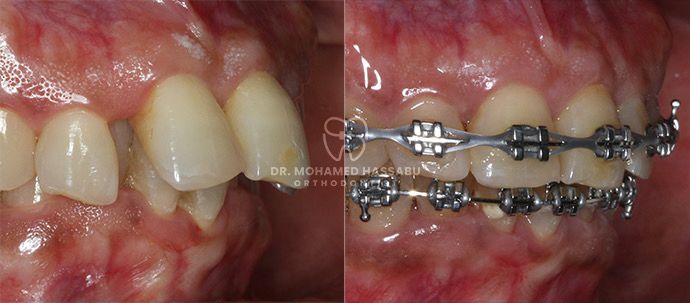

Traditional Braces:

Traditional braces, which have been proven effective over time, use metal brackets and wires to gently shift teeth into their correct places. Your child can add colorful bands to personalize their braces and make them uniquely theirs.

Ceramic Braces:

Ceramic braces for teens are less noticeable than metal braces, as they blend with the natural color of your child’s teeth. They are an excellent option for those who desire a more discreet treatment.

Damon Braces:

Damon Braces are innovative self-ligating braces that use a sliding mechanism, reducing discomfort and treatment time. They are suitable for kids and teens who want a faster and more comfortable orthodontic experience.